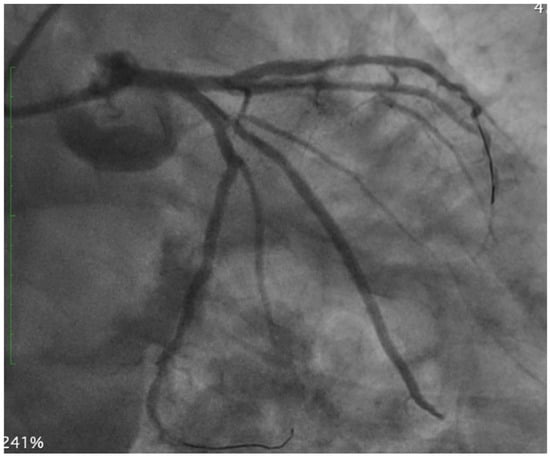

Coronary CT Angiography for PCI Planning and Guidance: A Comprehensive Narrative Review

by Lorenzo Fargione, Pietro Laforgia, Thomas Hovasse, Bernard Chevalier, Nicolas Amabile, Francesca Sanguineti, Stephane Champagne, Thierry Unterseeh, Antoinette Neylon, Neila Sayah, Jerome Garot, Lisa Simioni, Mario Togni, Stephane Cook, Hakim Benamer, Livio D’Angelo, Philippe Garot, Mariama Akodad and Ioannis Skalidis

Coronary computed tomography angiography (CCTA) is increasingly recognized as a comprehensive tool for planning percutaneous coronary intervention (PCI). By integrating plaque morphology, calcium burden, and CT-derived coronary physiology, CCTA enables non-invasive assessment of lesion complexity and supports precision-guided revascularization. This narrative review synthesizes [...] Read more.

Coronary computed tomography angiography (CCTA) is increasingly recognized as a comprehensive tool for planning percutaneous coronary intervention (PCI). By integrating plaque morphology, calcium burden, and CT-derived coronary physiology, CCTA enables non-invasive assessment of lesion complexity and supports precision-guided revascularization. This narrative review synthesizes current evidence on CT-guided PCI from original studies, registries, expert consensus documents, and international guideline recommendations. The literature was identified through PubMed, Embase, and Google Scholar, focusing on CCTA-based plaque characterization, calcium assessment, bifurcation and ostial lesions, chronic total occlusions (CTO), FFR-CT, virtual PCI simulation, and fusion imaging. Particular attention was given to contemporary investigations such as SYNTAX III, P3, and the ongoing P4 trial. CCTA reliably characterizes stenosis severity, plaque distribution, and calcification, demonstrating strong concordance with intravascular imaging. CT-based measurements support accurate stent sizing, prediction of calcium modification requirements, and identification of high-risk features in bifurcation and ostial disease. In CTO PCI, CCTA enhances visualization of proximal cap morphology, occlusion length, tortuosity, and distal vessel quality, outperforming angiographic scoring systems. CT-derived physiology and virtual PCI planning improve lesion selection and allow prediction of post-PCI hemodynamics. Emerging technologies—including photon-counting CT, artificial intelligence-assisted plaque analysis, and CT–fluoroscopy fusion—further expand the applicability of CT-guided PCI. The ongoing P4 trial is expected to provide definitive validation of CT-guided PCI and may support its incorporation into routine clinical workflows. Full article